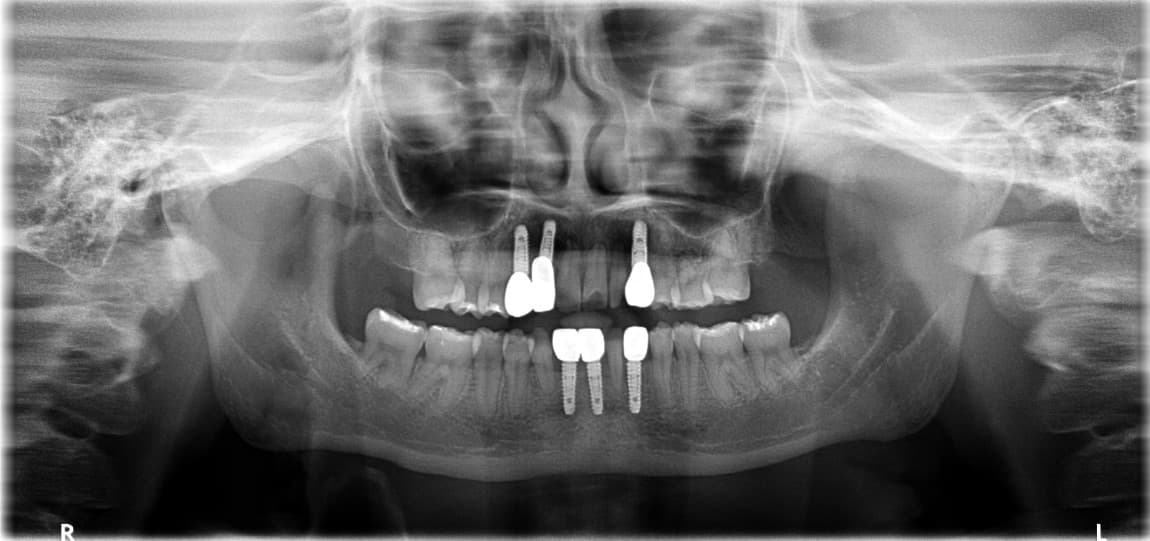

Phục hồi toàn hàm

Những trường hợp sức khỏe răng miệng bị hủy hoại hoàn toàn

được phục hồi trở lại cuộc sống bình thường

Điều trị tổng thể bởi bác sĩ chuyên khoa Phục hình

Bác sĩ phục hình của chúng tôi kết hợp tối ưu các phương pháp điều trị bao gồm Implant, răng sứ và cầu răng để tạo ra kết quả tốt nhất với chi phí hợp lý.

Phục hồi toàn hàm · Ông O●● · Nam, 60 tuổi